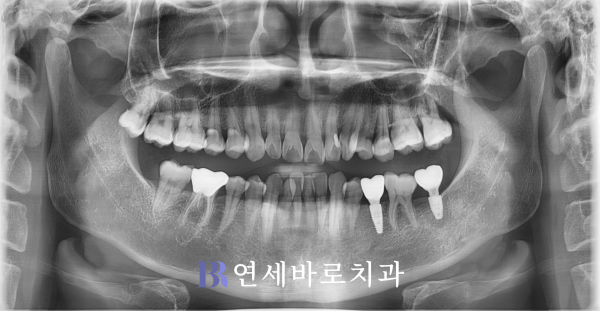

지금부터 알아볼 환자분께서는

영구치 소실로 임플란트가

필요하다면서 찾아오셨습니다.

왼쪽의 제2대구치와 더불어

그 앞의 작은 어금니가 빠져

매식체를 식립해야 할 필요가

있는 것으로 판단되었습니다.

여러분께서 좀 더 자세하게

확인해보실 수 있으시도록

사진을 더 확대해보았습니다.

빨간색 사각형으로 매식체가

들어갈 위치를 표시했습니다.

탈락한 곳이 오래 방치되어

어금니가 앞으로 기울었네요.

뿐만 아니라 상악에서는

큰 어금니가 사랑니에 밀려

밑으로 내려온 상태였습니다.